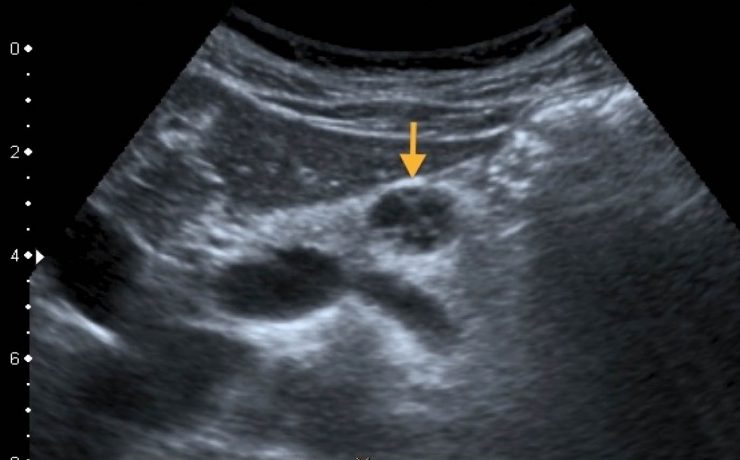

Mastitis granulomatosa idiopática

La mastitis granulomatosa idiopática es un proceso inflamatorio mamario benigno, poco frecuente, de origen desconocido. Se presenta en mujeres en edad reproductiva, entre los 17 y 42 años de edad. El diagnóstico se realiza por exclusión; para ello se utiliza ultrasonido, biopsia por aspiración de aguja fi na o biopsia